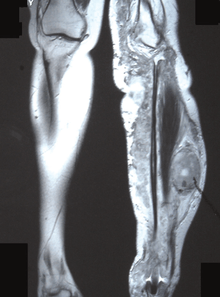

Diagnosis

The most conclusive test for a patient with a potential neurofibrosarcoma is a tumor biopsy (taking a sample of cells directly from the tumor itself). MRIs, X-rays, CT scans, and bone scans can aid in locating a tumor and/or possible metastasis.